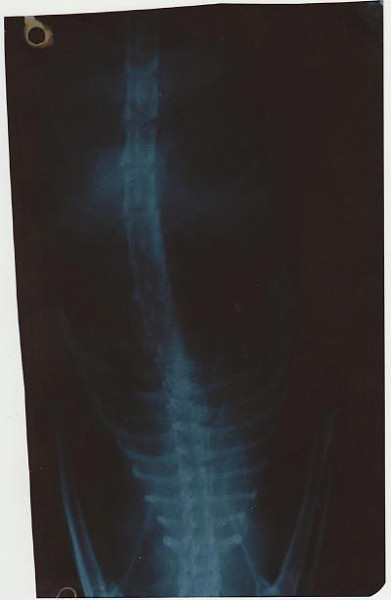

Легкие рентген 80% мутные

после лечения первого 70%

далее возврат к 80%

После последнего курса не делал, но судя по дыханию 65- 75%

Снимок неинформативен. Нельзя по такому снимку говорить об отёке или не отёке лёгких, и тем более, о его причине и лечении.

Проблема в лёгких, наверняка есть, судя по симптомам, но это может быть как отёк, так и свободная жидкость, так и новообразование. Лечение принципиально разное.

Рентген нужно переделать, в боковой проекции.